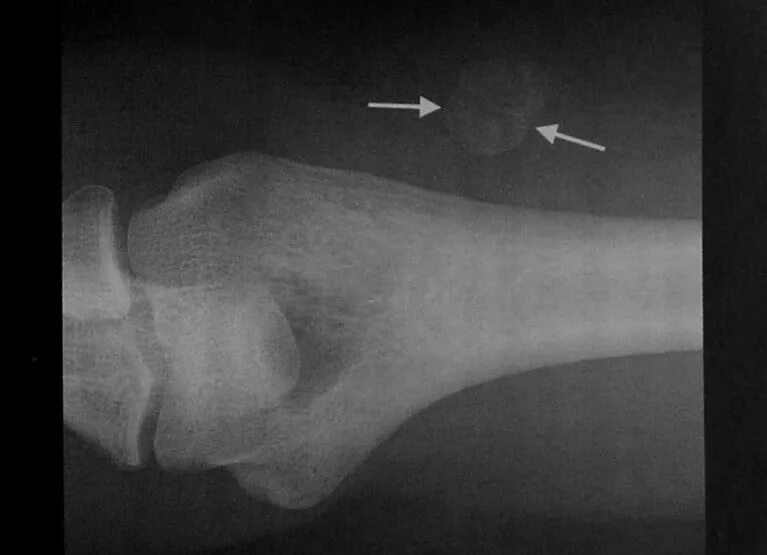

Оссифицированный миозит